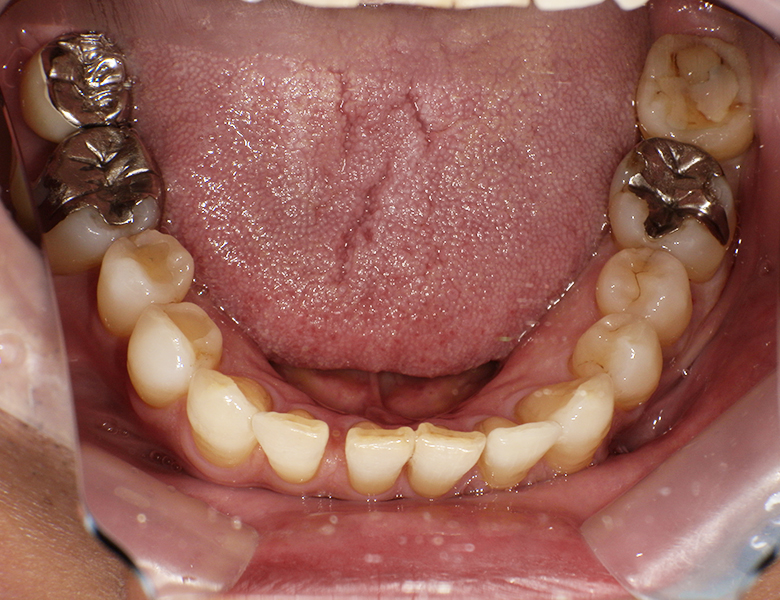

治療前 ![]() |

左下の第一大臼歯に入っている金属の詰め物が古くなり、見た目が気になるとのことで来院されました。金属の劣化による違和感もあり、白い歯で治療したいというご希望がありました。 |

左下の第一大臼歯には金属修復物が装着されており、経年的な劣化と変色が認められました。適合精度の低下も見られ、二次う蝕のリスクが高い状態でした。また、金属色が目立つことによる審美障害も認められました。 |